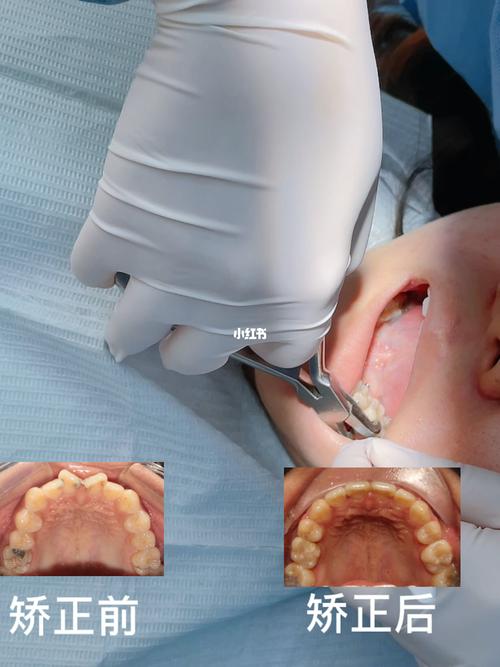

传统矫正需分阶段更换弓丝:先用镍钛圆丝排齐牙列,再用不锈钢方丝配合“扭转簧”“链状皮圈”等附件施加旋转力,通过“旋转-控根”两步法将牙冠与牙根同步调整;隐形矫正则需每1-2周更换一副牙套,每副牙套上设计“附件”(如小凸点)增强牙齿抓持力,计算机模拟确保每一步旋转角度在安全范围内;舌侧矫正因托槽位置特殊,需个性化定制弓丝与托槽,通过“三维力系统”精细控制牙齿移动。

第三阶段:保持阶段